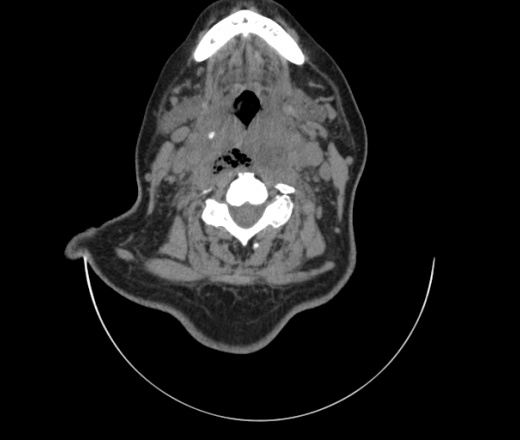

Женщина поступила в х/о спустя 4 дня после того как при употреблении карася подавилась костью.

Наличие газа в средостении на протяжении тел С2-С6 (медиастинальна эмфизема); рыбная кость на уровне тела С6.

При всем уважении, но говорить о медиастинальной эмфиземе, оценивая мягкие ткани шеи, как-то слишком резко. На мой взгляд, это ретрофарингеальное пространство.

Эвакуировали почти 100мл гноя. Но кость не смогли найти. Думаю что она даст дальнейшее ослоднение. Эндоскопически за черпалонадгортаной звязкой не смогли зайти в пищевод, все мягкие ткани отечные, просвет пищевода сдавлен. По всей видимости параэзофагеальная клетчака тоже задействована. Эмпиема, если ее можно так назвать, незнаю как правильно дошла до уровня яремной вырезки. Чем закончиться напишу. Ждем медиастинита.

Согласен с Вами; конечно, наличие газа в клетчатке ретрофарингеального пространства (затмение с опечаткой..). К сожалению, процесс "продвигается" к медиастиниту. Но почему никто, не отмечает наличие рыб. кости; или это для Всех очевидно?

Кость то мы сразу выявили, размеры где то 17*2мм, но ее так и не получается найти в этой каше